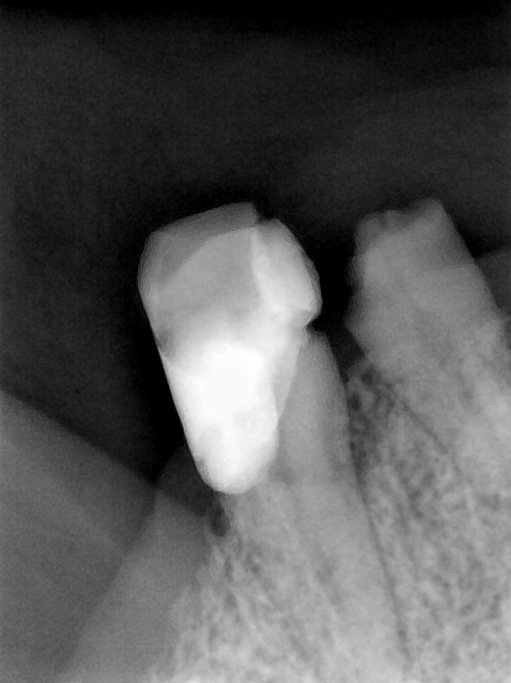

CR/DR 牙齿分割阶段记录

当前进展

- 完成了 CR/DR 牙齿相关分割训练

- 当前结果已经达到阶段预期,但仍有细节问题需要继续处理

相关测试

遇到的问题

- 训练过程中出现过 mask 下移问题

- 部分结果会出现 box 填充异常

- mask 边缘仍然有比较明显的锯齿感

第二版算法问题测试

Updated: 2026-04-13(更新日期)

| 第一版 | 第二版 | 是否解决 | |

|---|---|---|---|

![]() | ![]() ![]() 边角识别有问题 龋齿识别不全 牙髓识别不全 | ![]() | 解决 |

![]() | ![]() 边角识别有问题 识别信息有误 自查(牙冠识别不全) | ![]() | 解决 |

![]() | ![]() ![]() 边角识别有误 大范围填充识别遗漏 | ![]() | 解决 |

![]() | ![]() 识别信息不全 | ![]() | 解决 |

![]() | ![]() ![]() 边角问题 牙胶识别不全 牙冠识别不全 | ![]() | 解决 |

![]() 换图片 | ![]() | ![]() 牙冠部分稍微白了一些就识别成小范围修补,部分判断异常 | 部分解决,修复类略敏感,牙冠部分稍微白了一些就识别成小范围修补,部分判断异常。 |

![]() | ![]() ![]() 牙冠识别不全 牙髓不全 根尖炎龋齿识别有误 | ![]() | 解决 |

![]() | ![]() | ![]() | 解决 |

![]() 换图片 | ![]() | ![]() | 解决 |

![]() | ![]() 牙冠识别有误 | ![]() | 解决 |

![]() 换图片 | ![]() ![]() 边角识别有误 | ![]() 修复类敏感 | 部分解决,图像过白,导致修复类判断异常。 |

![]() 换图片 | ![]() 牙冠识别不全 | ![]() 修复类敏感 | 部分解决,图像过白,导致修复类判断异常 |

结论:修复类出现了不鲁棒的情况,后续需要加入轮廓的扩充数据进行增强。